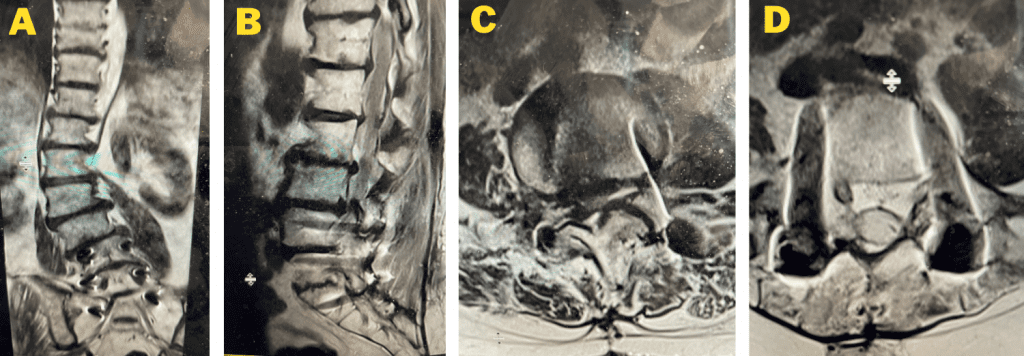

figure 1a and 1b lumbar stenosis

Figs 1a and 1b: T2 sagittal and axial lumbar MRI demonstrating severe L45 stenosis mainly secondary to thickened ligamentum flavum with a grade 1 spondylolisthesis at L45.

Lumbar stenosis is a fairly common condition I see in my office. Patients develop lumbar stenosis or narrowing of the spinal canal as a result of degenerative instability and laxity that is mainly age related. The body attempts to auto stabilize itself by forming stabilizing structures to compensate for instability such as thickening an already existing ligament or compensating by enlarging the facet joints which are the two regular joints on either side of the back of the spine in order to help improve stability. (Figs 1a and 1b) These structures are actually a form of arthritis and exert pressure on the canal in which the nerve sac travels through and the tunnel that the nerve leaves the spine. The spine does not know or care that the nerves are there and as a result the nerves get injured. The spine, at least the bony portion, is just taking care of itself. Patients are treated surgically for this by a procedure called a laminectomy which in essence restores the diameter of the spinal canal and the nerve tunnel by shaving away the arthritis. The trick of the laminectomy is to pick and dissect this sometimes soft and sometimes hard material from the nerve sac membrane for which it has been compressing for many years. Sometimes that material is really impaling the membrane which is called the dura. It is very important to do this gently in the manner in which we have been trained and avoid a tear or a leak in this membrane. This can happen and can be repaired with a stitch and some biological glue.